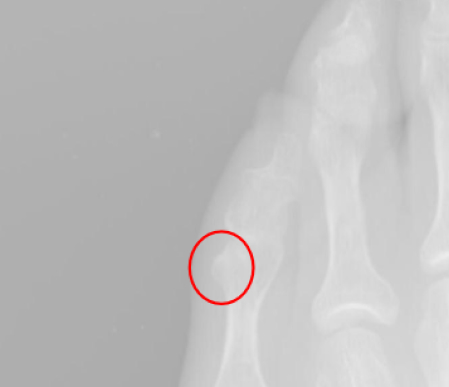

En las imágenes vemos osteofitos que en la piel generan un heloma dorsal del 5º dedo.